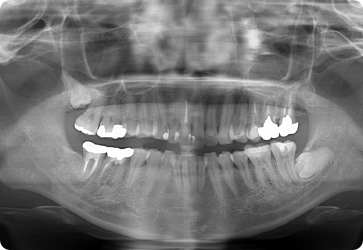

歯周病レントゲン検査・口腔内写真

歯を支えている顎の骨(歯槽骨)の損失具合がわかります。